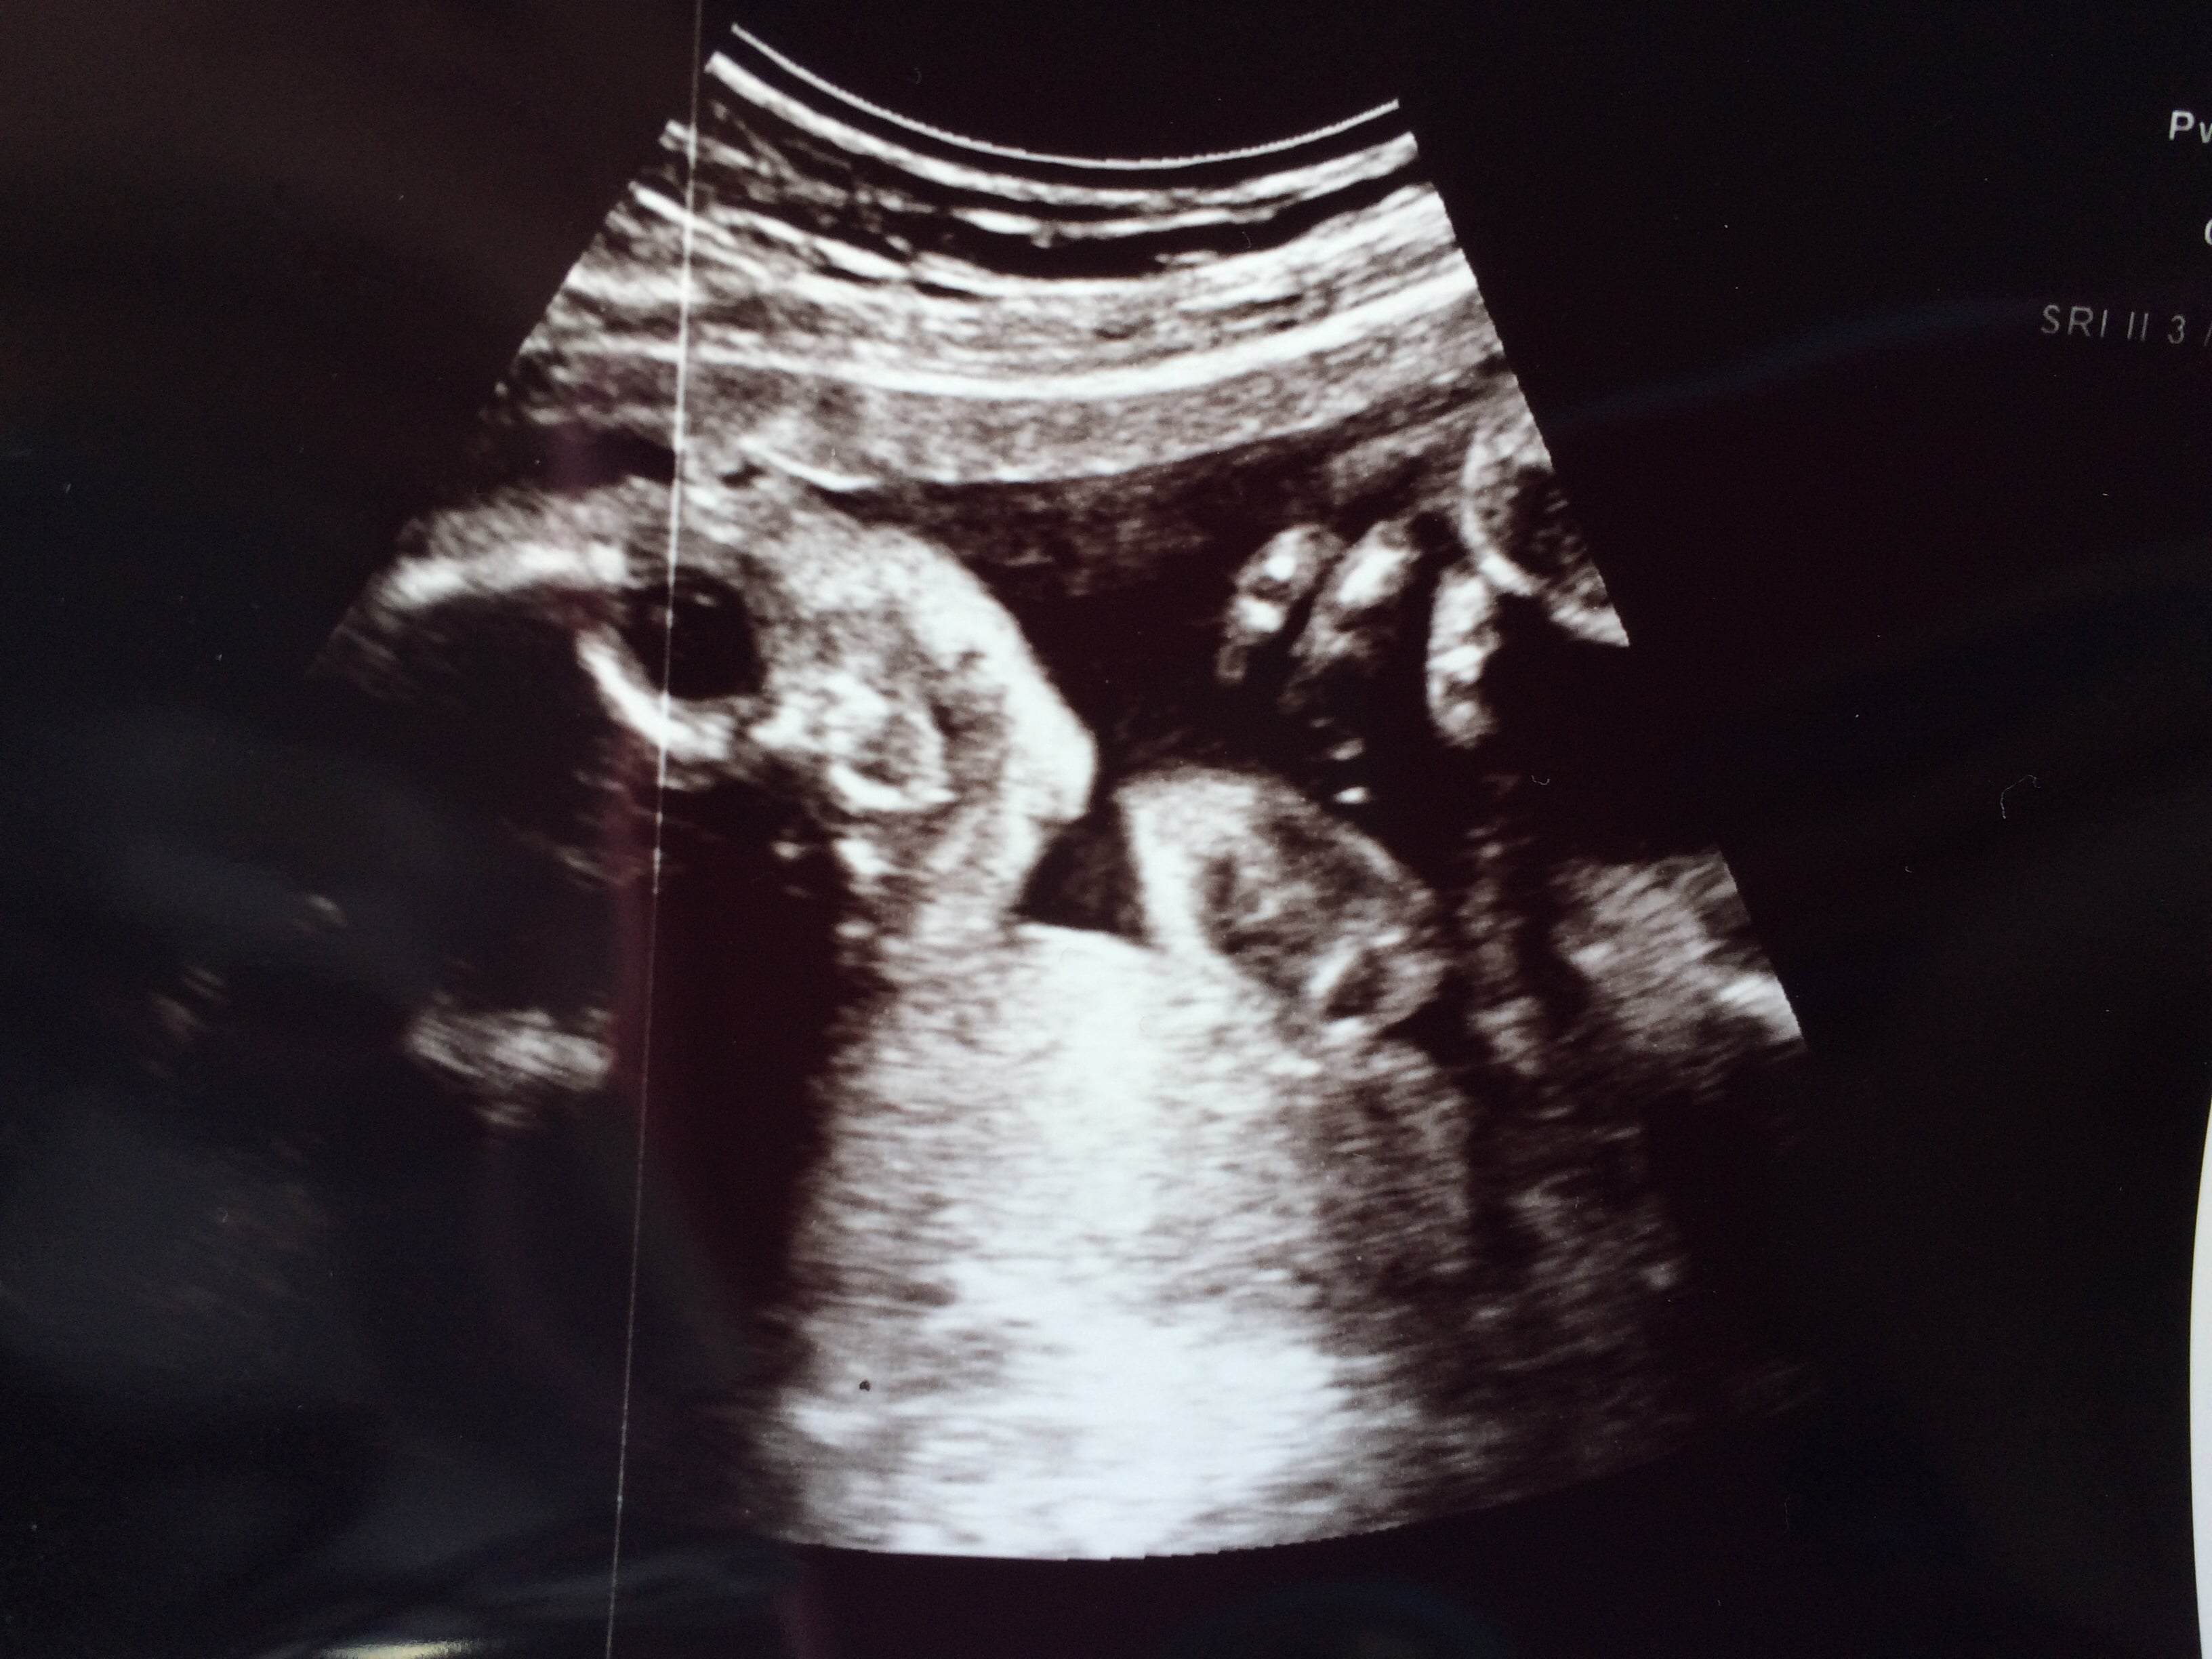

Appt went well. Just realized today is V day for me! Dr said baby is around 1lb 9oz and he was so active and chubby! Last month he was head down and now he flipped. His head is on my right side at the top, butt right on my cervix, and feet and legs on my left side. That would explain the insane and painful movement I've had. He's looking great though! I hope everyone had a great day!